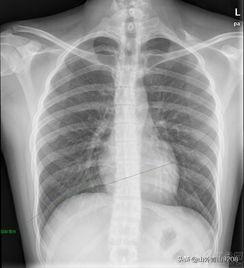

病例一老年男性患者,是一个同事的父亲,之前体检拍过胸片未见异常,6个月后因为其它问题入院,常规拍胸片发现右下肺一个团块影,做了个胸部CT,右下肺就是一个大肿块,考虑肺癌合并阻塞性肺炎,完善检查后做了手术,病理就是肺鳞癌,合并大片炎症并脓肿形成。这一例发展真的很快,回过头来再仔细观察6个月前拍的胸片,的确看不到明显异常,是不是真的没问题不敢说,因为当时没有做CT,但是6个月后的胸片是可以明显看到肿块影的。可以说他算是不幸之中的大幸吧,发现的还算及时,没有转移,可以手术根治。资料如下图,上图为胸片,下图为CT。

病例二这是一个老年女性,应该也不算老,五十几岁,医院的一个同事,职工体检拍了胸片,没看到什么问题。当时她问我们胸部是不是没问题,我们说胸片是正常的,但是因为她五十几岁了,建议再做个胸部CT,因为胸片有些东西真看不到,不怕一万就怕万一,这个同事听从了我们的建议,做了胸部CT,果真发现右下肺有一个很小的病灶,大约1cm左右,考虑早期肺癌。过几天做了手术,病理就是肺腺癌。应该说非常幸运,因为发现的早,手术切了基本就什么事都没了,也不用放化疗,术后没几天又继续上班了。资料如下图,上图胸片,下图CT。

病例三这是一个老年女性,也是同事的家属。6年前同事带到过医院做了一次比较全面的体检(包括胸部CT),结果都挺正常的。后来同事每年想带她到医院体检就不来了,因为感觉自己身体挺好,平时也没什么不舒服,而且之前体检过都没问题。直到最近半年发现身体瘦了很多,有点咳嗽,经不住同事劝,终于到医院检查,检查结果一出来同事眼泪也跟着出来了。肺癌晚期,右下肺癌并肺门淋巴结多发转移,做了PET发现远处也有转移了。很遗憾,同事后悔莫及,或许自己每年坚持一下带到医院体检就不会是这样的结果了,但一切都迟了。资料如下图,左图胸片,右图CT。